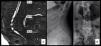

Tras la colocación de la paciente en decúbito supino, esta se inestabilizó de nuevo. La presión arterial sistólica se redujo a 37mm Hg durante 3-5min, siendo necesario el uso de dopamina, cristaloides y fluidos para su estabilización. No fueron necesarias maniobras de resucitación. Después de la estabilización de la paciente y bajo monitorización fue trasladada a rayos, donde se realizó, bajo indicación del radiólogo intervencionista, en primer lugar un angio-TAC que descartó sangrado de grandes vasos o sangrado activo intraabdominal; tan solo se evidenciaba un hematoma sugerente de sangrado activo en la región paravertebral lumbar derecha (fig. 2A). Una vez descartado el sangrado de grandes vasos se procedió a la realización de una arteriografía selectiva a través de la arteria femoral común derecha con un catéter tipo cobra, realizando un cateterismo retrógrado hasta alcanzar la arteria lumbar derecha L5. Tras la introducción de contraste se puso de manifiesto la presencia de una lesión pseudoaneurismática con extravasación activa de contraste dependiente de arteria lumbar L5 derecha (fig. 2B). Se procedió a la embolización de dicho pseudoaneurisma sangrante con microesferas de 300-500micras y posteriormente con microcoils de 3×3. Una nueva inyección de contraste confirmó el cese de la extravasación de contraste a nivel del pseudoaneurisma y, por tanto, el cese del sangrado (fig. 2C). Desde el comienzo del sangrado hasta la estabilización mediante la embolización la paciente precisó el uso de fármacos vasoactivos y transfusión de 5 concentrados de hematíes, 700ml de plasma fresco, 1g de fibrinógeno, 1.000cc de coloides y 2.500cc de cristaloides.

A) TAC abdominal con contraste; corte a nivel de cuerpo vertebral L5. Flecha verde: arterias ilíacas con contraste. Flecha naranja: hematoma paravertebral derecho. B)Arteriografía: extravasación de contraste a nivel de arteria lumbar derecha L5 sugerente de pseudoaneurisma. C)Arteriografía postembolización: se observan microcoils en la raíz de arteria lumbar L5 derecha sin paso de contraste.